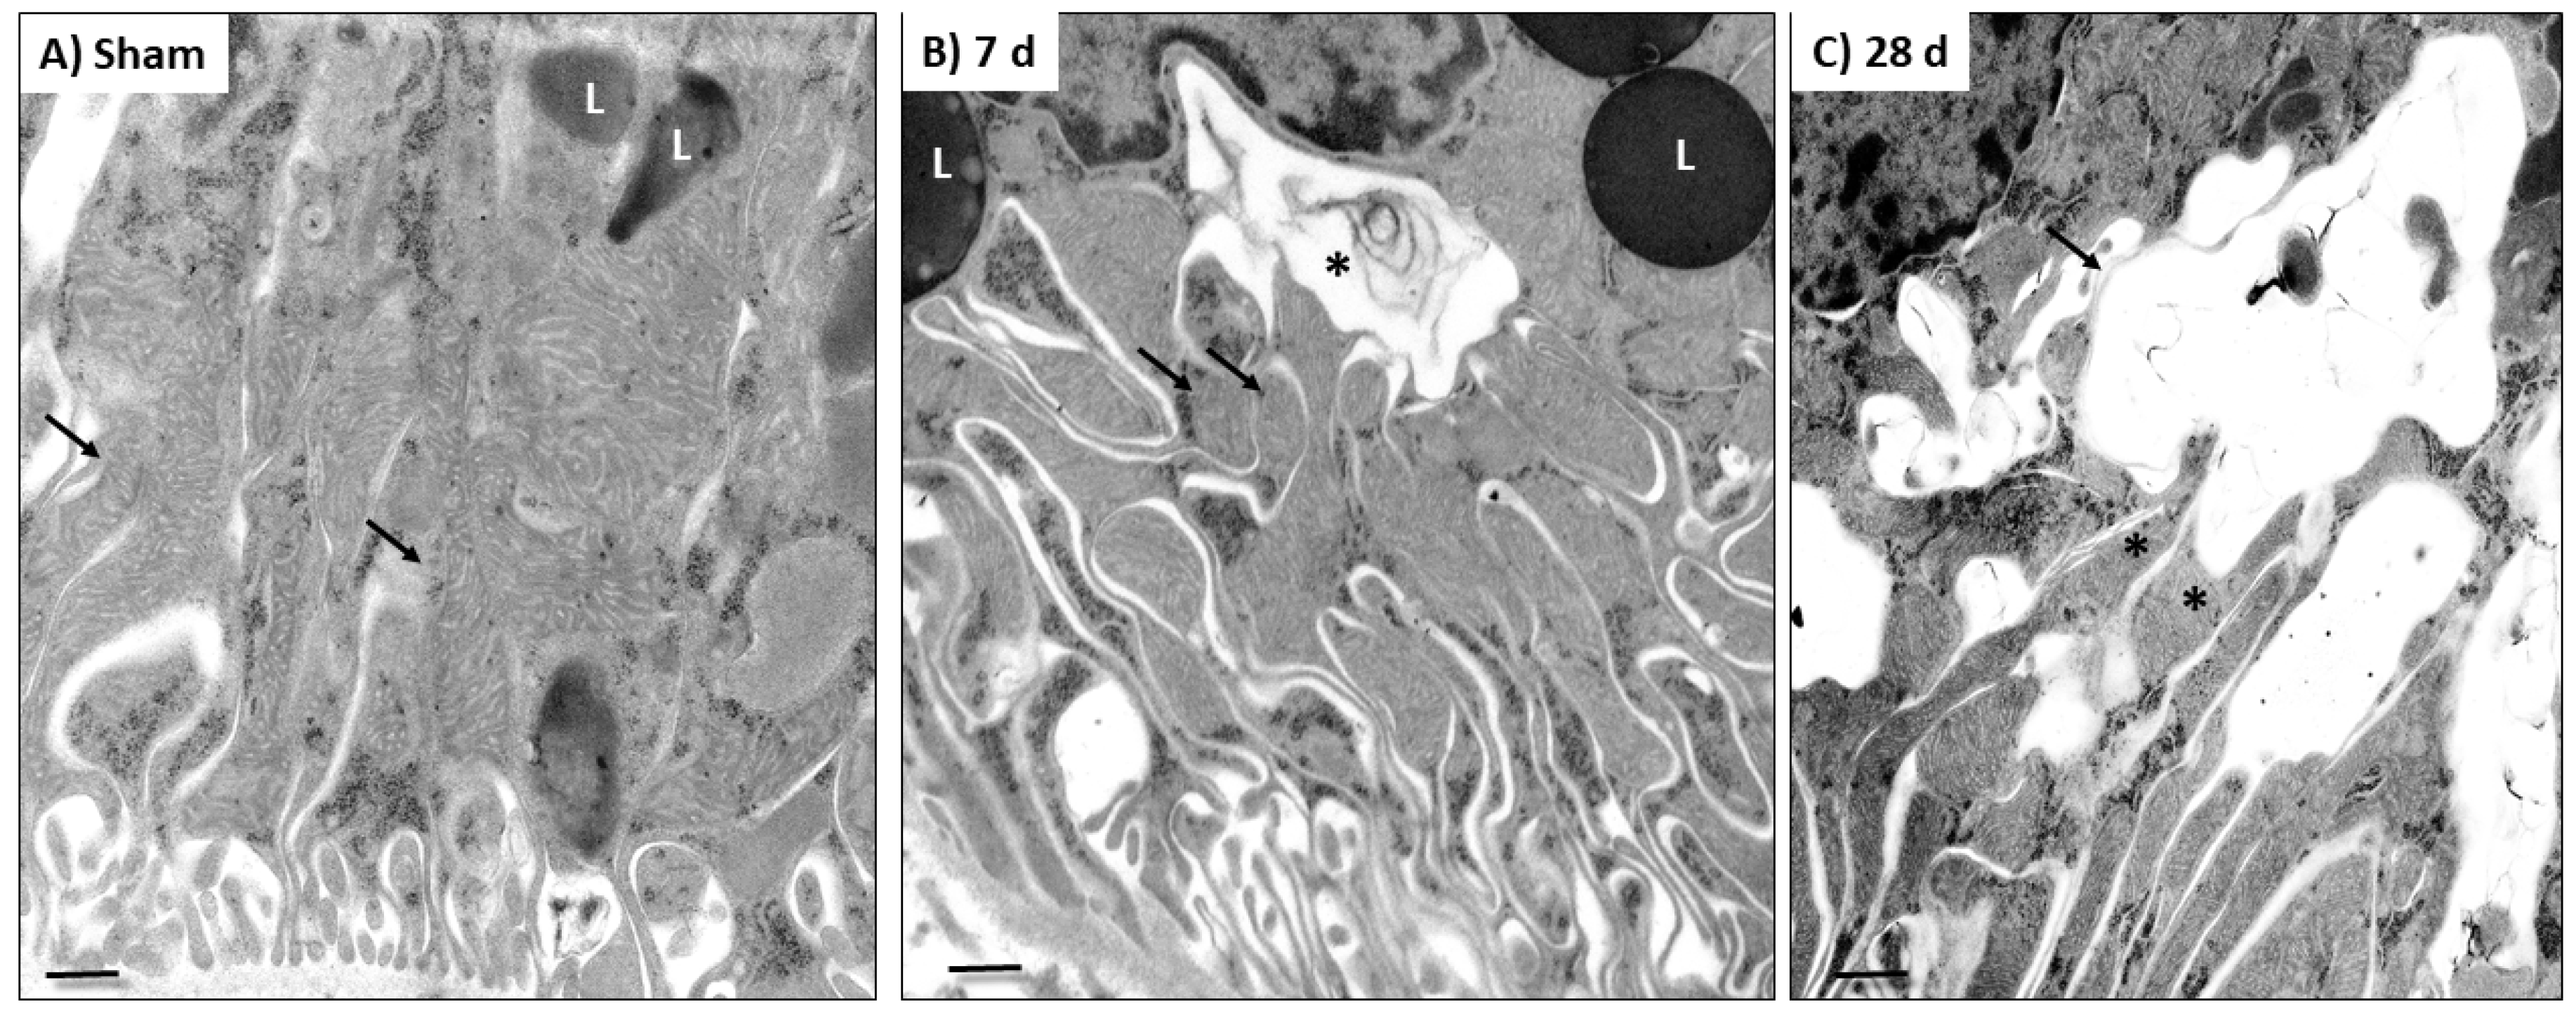

2.4. Electron Microscopy Study

3.3. 5/6Nx Induces the Increase in Mitochondrial Fission and the Reduction in Mitochondrial Fusion